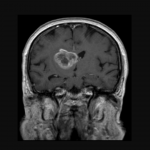

Terry Fox Research Institute supports trailblazing work of biologist helping brain cancer patients

March 7, 2018 —

Brain cancer research in Manitoba has received a boost with news that a U of M researcher has won a prestigious cancer research award